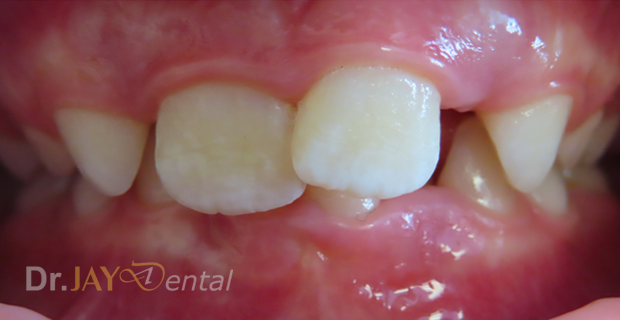

CASE 16

Misaligned teeth , crowding resolving in 3 months , patient still continuing with treatment. Arch expansion and myofunctional therapy

Before

After